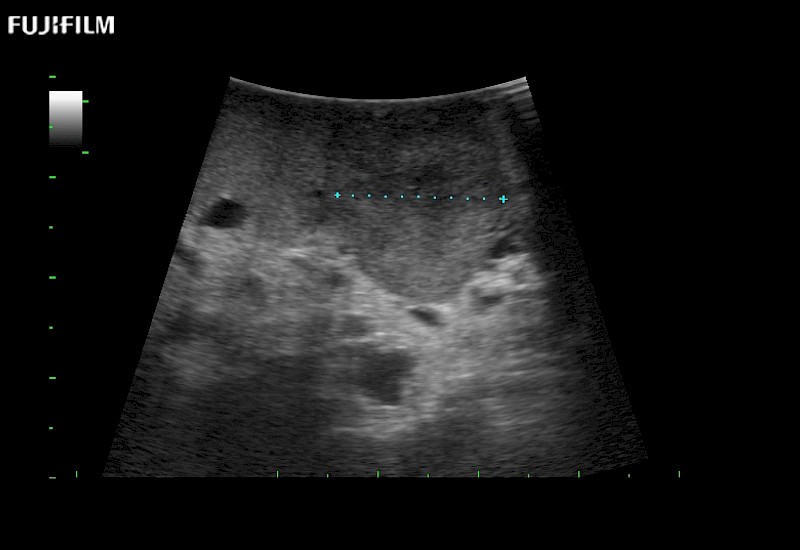

Extraordinary high-resolution digital imaging

- Exceptional near and far-field resolution

- Instant feedback on tumor margin delineation

- Valuable information to guide tumor resections

- Exceptional near and far-field resolution

- Instant feedback on tumor margin delineation

- Exceptional near and far-field resolution

- Exceptional near and far-field resolution

- Instant feedback on tumor margin delineation

- Exceptional near and far-field resolution

- Instant feedback on tumor margin delineation

- Exceptional near and far-field resolution

- Instant feedback on tumor margin delineation

- Exceptional near and far-field resolution

- Instant feedback on tumor margin delineation

- Valuable information to guide tumor resections

- Exceptional near and far-field resolution

- Instant feedback on tumor margin delineation

- Valuable information to guide tumor resections

- Exceptional near and far field resolution

- Instant feedback on tumor margin delineation

- Valuable information to guide tumor resections

- Exceptional near and far-field resolution

- Instant feedback on tumor margin delineation

- Valuable information to guide tumor resections

- Exceptional near and far field resolution

- Instant feedback on tumor margin delineation